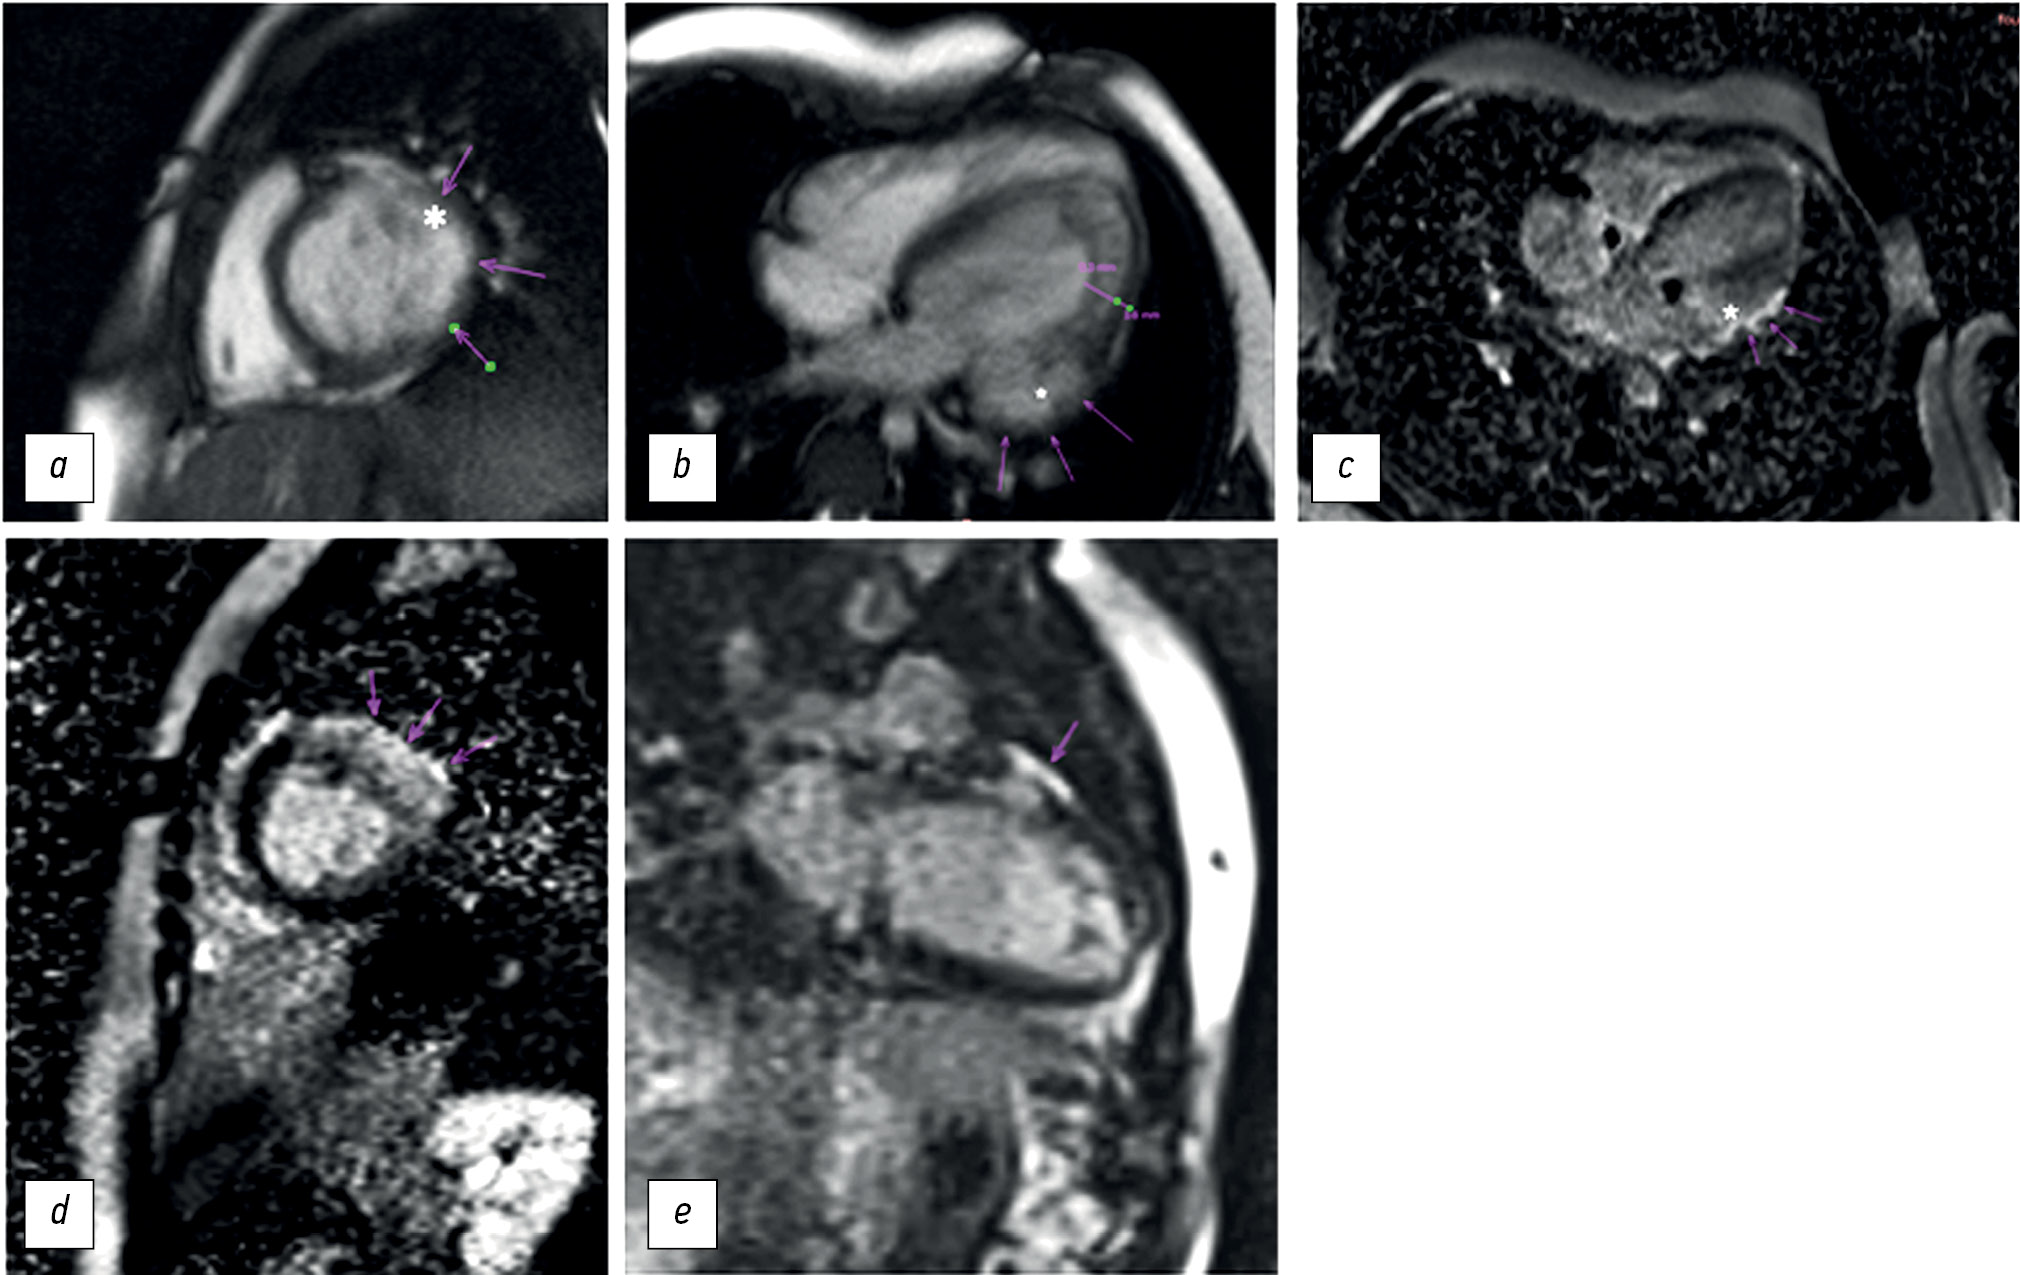

During hospitalization, echocardiography revealed LV dilatation, increased trabecularity of the apex and lateral wall of the LV, sac-like bulging of the lateral-basal part as aneurysm, and possibly deep trabeculae (Figure 1a–c). The echocardiography revealed a decline in LV systolic function and a 48% LV ejection fraction. There was minimal regurgitation on the tricuspid, mitral, and pulmonary valves.

Fig. 1. Transthoracic echocardiography (cardiac sensor, two-dimensional scanning) of a 6-year-old patient with myocardial non-compactness and left ventricular aneurysm: a - in the apical four-chamber projection in gray scale mode, bulging of the left ventricular wall and myocardial non-compaction are noted, the ventricle is connected to the aneurysm (asterisk); b — in the apical four-chamber projection in the color Doppler mapping mode, a large anechoic formation is determined (aneurysm is indicated by an asterisk) with pronounced trabeculation in the area of the apex and lateral walls of the left ventricle; c — in a three-chamber projection in the color Doppler mapping mode, the aneurysm (asterisk), inlet and outlet of the left ventricle are determined.